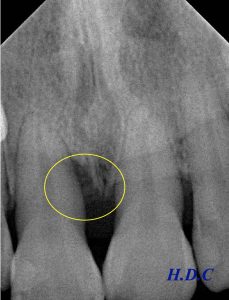

歯周基本治療(歯ブラシ指導や歯石取りなど)後、患者さんの同意を得て、エムドゲインを用いた歯周組織再生療法を行いました。

左のレントゲンが初診時、右のレントゲンがエムドゲイン治療後2年半経過時です。

歯周病で溶けてしまった骨の再生が確認できます(黄色い枠の中)。外科治療前に6mmあった歯周ポケットも、2mmに改善しました。

今後、セルフケア(患者さん自身によるブラッシング)とプロフェッショナルケア(歯科医院でのクリーニング)をしっかりと継続すれば、この状態を長く保てるのではと思われます。